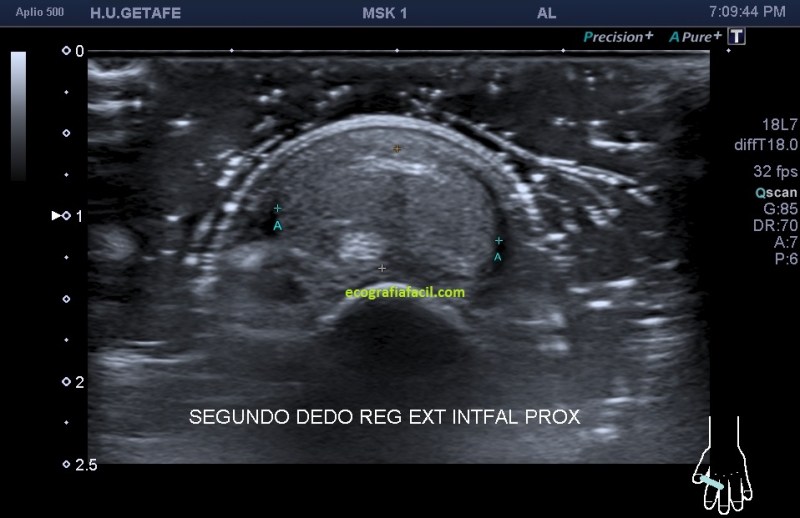

Hoy vas a ver el caso de un paciente que acude por un bulto de largo tiempo de evolución en la región extensora del segundo dedo justo a la altura de la articulación interfalángica proximal. Acude a su médico al observar crecimiento lento y por el volumen, ligera incapacidad a la hora de flexionar y extender el dedo. Es indoloro, aunque por el tamaño, estira la piel, sin llegar a afectarla. Es blando a la palpación.

Exploración ecográfica:

Seguimos en este post a pies juntillas el protocolo en la exploración de bultos, localizar, estudiar, medir y vascularización. Aquí el protocolo se hace más que importante sobre todo en las imágenes de la 1 a la 4 ya que es vital, en estos casos donde las estructuras que participan del estudio son tan pequeñas, saber discernir bien las diferentes ecoestructuras implicadas. Es decir, la localización y el estudio pormenorizado, con la máxima calidad de imagen que podamos conseguir ajustando los parámetros técnicos que te he explicado tantas veces, en este caso fueron definitivos para la calidad del estudio.

El tendón extensor es una ecoestructura muy fina, que puede pasar desapercibida si no tenemos una alta calidad de imagen, en la imagen 4 lo tienes delimitado entre dos líneas rosas, por si en la imagen 3 te había costado situarlo, repito, fundamental en este estudio su caracterización.

La anatomía de la ecoestructura, sobre todo de la imagen 3 deja muy a las claras uno de los objetivos del estudio, que era valorar la independencia del tendón extensor del dedo respecto del tumor, es decir, que el tendón, hueso y piel estuviesen indemnes como así fue.

La ecoestructura tumoral era hiperecogénica, ovalada, heterogénea, con ligera presencia de líquido alrededor del tumor, tumor que no infiltraba anatomía colindante y  cuya que además poseía muy poca vascularización…

Cortes en eje corto y eje largo para poder hacer medidas, imágenes 5 y 6 y luego, el doppler, 7 y 8 donde se demostró mínima vascularización interna y dos «grandes» vasos laterales, arteriales.

El radiólogo después de estudiar las imágenes dictamina alta sospecha de Tumor de Células Gigantes sin necesidad de realizar pruebas a modo de ampliar el estudio, que suele ser RMN, que como digo, en este caso, no fue necesario.